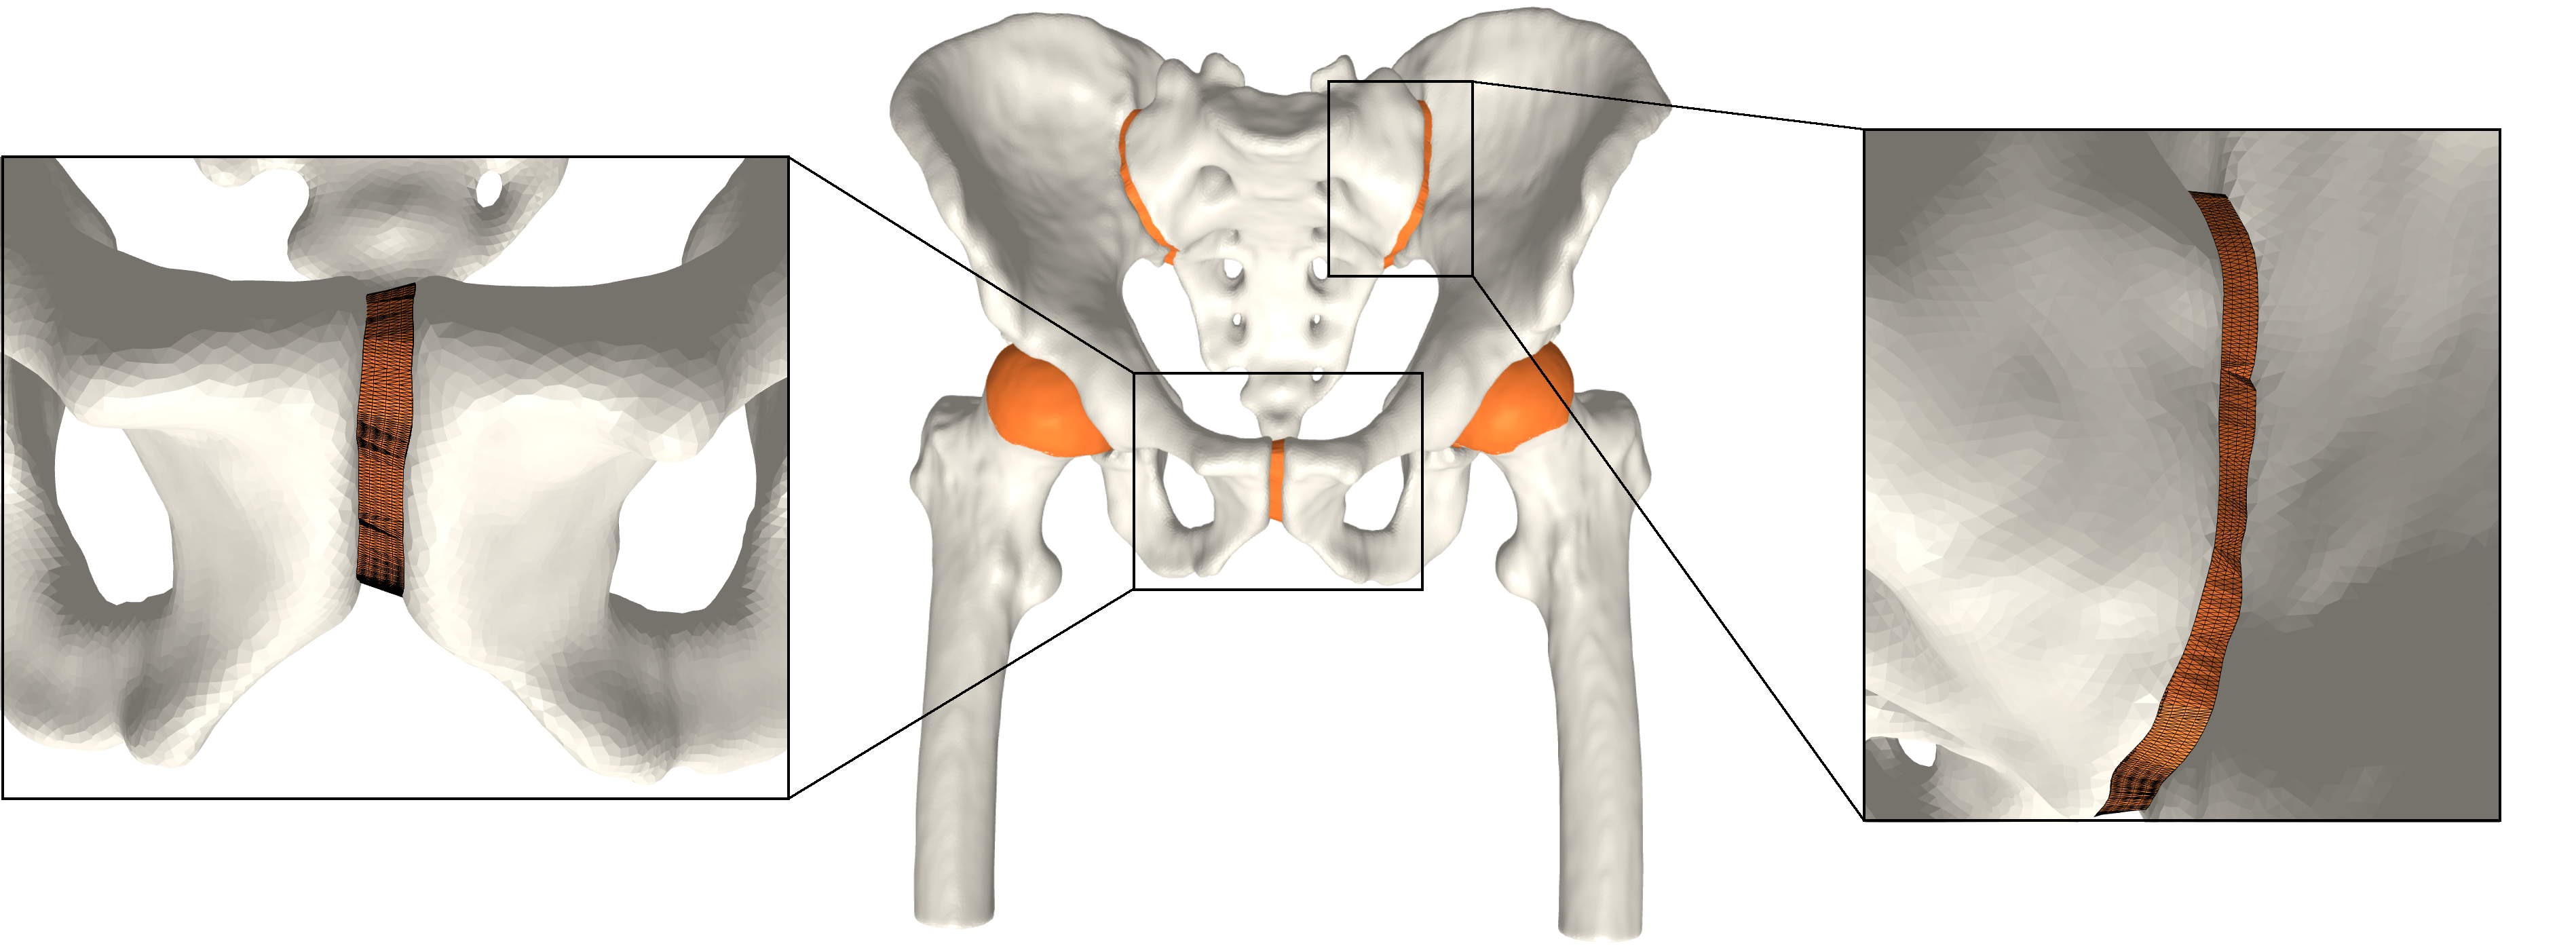

The FE analysis results show that the generated models produce smooth stress patterns in a pseudo stance without any geometry-related convergence issues. As mentioned in section 4, these results only serve as a verification test of simulation properties. We need a more advanced simulation setting to model a real stance position. We leave this for future work. Moreover, we believe that minor modifications will estimate the shoulder joint cartilage since it has a similar ball-in-socket structure. Fig. 5 shows early evidence of generalization. In contrast, other joints, such as the knee joint, are challenging. We leave other joint types for future work.

Refer to caption

(a)

(b)

(c)

Figure 5: a) All generated cartilages. Zoom boxes highlight the pubic and sacroiliac joint cartilages. b) Shoulder joint cartilage c) Femoral and tibial cartilage in the knee joint. Bone models are acquired from available datasets [3, 5, 4].